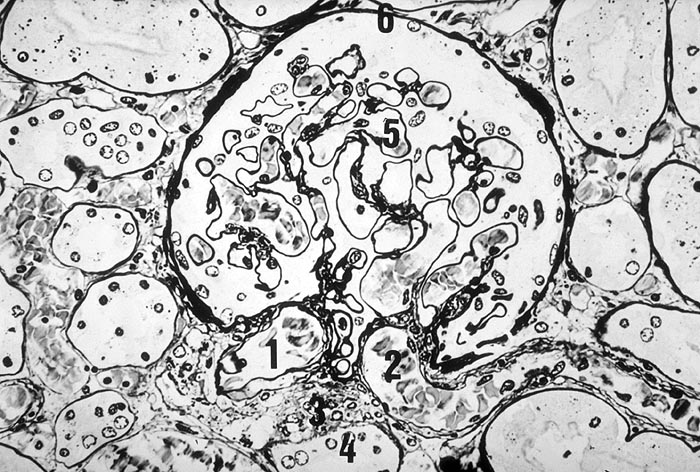

Die renale Mikroangiopathie bei Diabetes mellitus ist Folge einer Matrixstörung besonders charakterisiert durch eine Zunahme von Kollagen Typ IV in der mesangialen Matrix und in den Basalmembranen von Glomerula, Gefässen und Tubuli.

Im allgemeinen ist die Niere infolge von Glomerulumhypertrophie und Tubulushyperplasie vergrössert und derb, die Oberfläche ist granuliert. Bei schwerer Atherosklerose und fortgeschrittener Niereninsuffizienz kann die Niere auch normal gross oder verkleinert sein. Die Kombination von nodulärer Glomerulosklerose, hyalinen Schlingenkappen (=Proteinthromben in den Glomerulumschlingen (> 1916)) oder Kapseltropfen (> 1907) und Arteriolosklerose in Vas afferens und efferens ist beweisend für eine diabetische Nephropathie. Jede einzelne Läsion für sich genommen ist aber unspezifisch. Eine noduläre Glomerulosklerose kann auch vorkommen bei membranoproliferativer Glomerulonephritis (> 2652), Leichtkettenglomerulopathie oder Amyloidose (> 2019). Der nodulären Glomerulosklerose geht bei Diabetikern eine diffuse Glomerulosklerose (> 1906) voraus. Dabei zeigen die glomerulären Basalmembranen und das Mesangium eine progrediente gleichförmige Verbreiterung. Bei der nodulären und diffusen Glomerulosklerose handelt es sich aber wahrscheinlich um zwei pathogenetisch unterschiedliche, sich überlagernde Krankheitsbilder. Typisch bei Diabetikern ist im Unterschied zur arteriellen Hypertonie die Arteriolosklerose von Vas afferens und efferens (> 1911) und oft auch der Vasa recta. Intrarenale Arterien können eine Atherosklerose mit Atheromen zeigen. Subendotheliale Proteinablagerungen teilweise mit Verschluss der Glomerulumschlingen (Schlingenkappen) und knotige Proteinablagerungen in der Bowman'schen Kapselbasalmebran (Kapseltropfen) gehören zu den sogenannten exsudativen Läsionen (> 1919) (> 1920) der diabetischen Nephropathie und führen zu Synechien sowie zur globalen Glomerulosklerose. Gleichzeitig mit den Glomerulumveränderungen treten tubuläre Basalmembranverbreiterungen auf, später eine Tubulusatrophie und interstitielle Fibrose mit Begleitentzündung. Auch die Basalmembranen der peritubulären Kapillaren sind verdickt.

• Verbreiterung des Mesangiums mit Ausbildung von Knoten(noduläre Glomerulosklerose).

• Arteriolosklerose von Vas afferens und efferens (Gefässwandhyalinose durch Ablagerung von Plasmaproteinen und Lipiden in der Gefässwand).

• Verdickte Basalmembranen der peritubulären Kapillaren.

• Verbreiterung der tubulären Basalmembran.